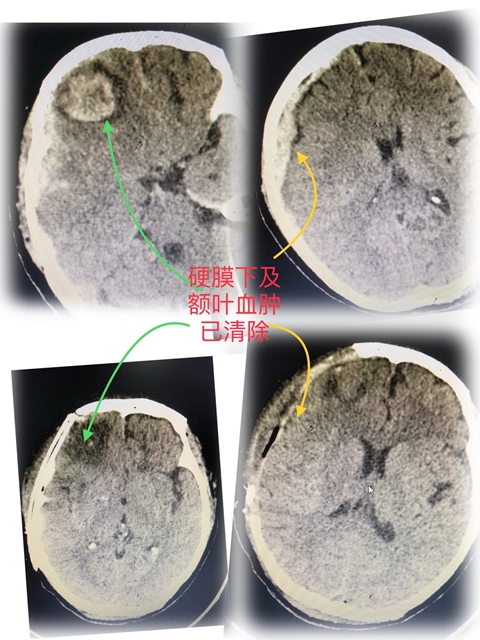

随后的CT扫描结果让在场的医护心里一紧。“右侧额颞顶部硬膜下血肿、脑疝形成”——这是神经外科的"红色警报",意味着她的部分脑组织已经被积血压得变形。

无影灯亮起。两院团队默契配合,快速完成了开颅血肿清除术+去骨瓣减压术。

经过2个多小时的手术后,李阿姨被他们联手从鬼门关拽回来了。

手术第二天,李阿姨的手脚活动就恢复正常。目前已经可以下床行走,即将康复出院。